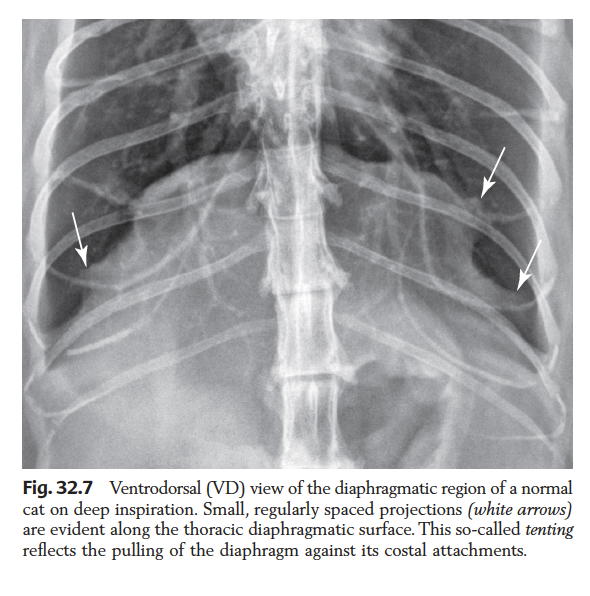

In what views does the diaphragm have a dome / mickey mouse shape?

Dome: DV thorax, VD mid abdomen

Mickey: VD thorax, DV mid abdomen